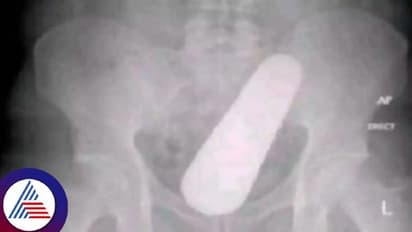

ಕೊಲಂಬಿಯಾದ ವ್ಯಕ್ತಿ ಹಲವು ವಾರಗಳಿಂದ ಕಾಲುಗಳಲ್ಲಿ ನೋವನ್ನು (Leg pain) ಅನುಭವಿಸುತ್ತಿದ್ದ. ಕೂರಲು, ಏಳಲು, ನಡೆಯಲು ಹೀಗೆ ಯಾವುದೇ ರೀತಿಯ ಚಟುವಟಿಕೆ ನಡೆಸಲು ಕಷ್ಟವಾಗುತ್ತಿತ್ತು. ಹೀಗಾಗಿ ಆತ ತಕ್ಷಣ ಚಿಕಿತ್ಸೆ (Treatment) ಪಡೆಯಲು ವೈದ್ಯರ ಬಳಿ ಹೋಗಿದ್ದಾನೆ. ವೈದ್ಯರು (Doctor) ಎಕ್ಸ್-ರೇ ಮೂಲಕ ಗುದನಾಳದಲ್ಲಿ ಏನಿದೆ ಎಂಬುದನ್ನು ಪರಿಶೀಲಿಸಿದ್ದಾರೆ.

ಈ ಸಂದರ್ಭದಲ್ಲಿ ಸೌತೆಕಾಯಿ ಸಿಲುಕಿ ಹಾಕಿಕೊಂಡಿರುವುದು ಗೋಚರಿಸಿದೆ. ಶಸ್ತ್ರಚಿಕಿತ್ಸೆಯ (Operation) ನಂತರ, ಸೌತೆಕಾಯಿ ತನ್ನ ದೇಹದೊಳಗೆ ಹೇಗೆ ಸಿಲುಕಿಕೊಂಡಿದೆ ಎಂದು ತನಗೆ ತಿಳಿದಿಲ್ಲ ಎಂದು ವ್ಯಕ್ತಿ ಹೇಳಿದನು. ಮಾತ್ರವಲ್ಲ, ಬಹಳಷ್ಟು ಸೌತೆಕಾಯಿಗಳನ್ನು ತಿನ್ನುವ ಕಾರಣ ಸೌತೆಕಾಯಿ (Cucumber) ಬೀಜದಿಂದಾಗಿ ಜೀರ್ಣಾಂಗ ವ್ಯವಸ್ಥೆಯೊಳಗೆ ಸೌತೆಕಾಯಿ ಬೆಳೆದಿರಬಹುದು ಎಂದು ತಿಳಿಸಿದನು. ವೈದ್ಯರು ವ್ಯಕ್ತಿಯ ಬಾಲಿಶ ಹೇಳಿಕೆಗೆ ಪ್ರತಿಕ್ರಿಯಿಸದೆ ಆತನನ್ನು ಮನೆಗೆ ಕಳುಹಿಸಿದರು.